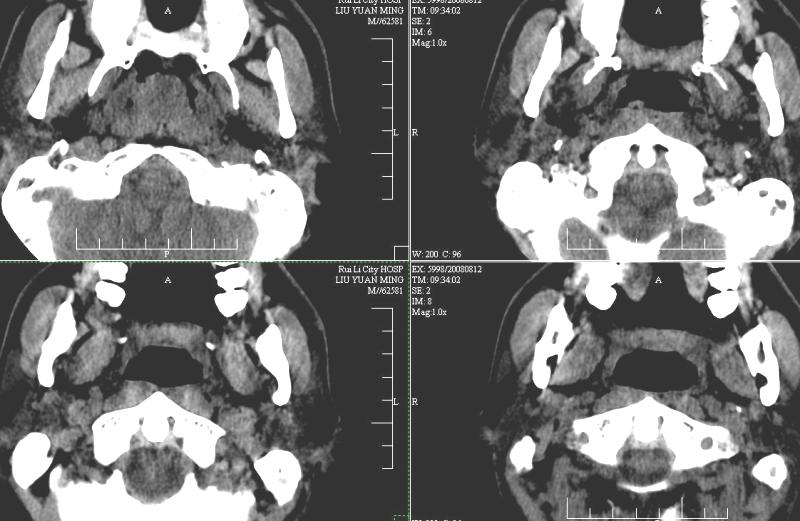

以下是引用ydx_74在2008-8-12 22:09:00的发言:[br]不考虑鼻咽癌。没有淋巴结肿大,没有颅底骨质破坏,咽隐窝、咽鼓管咽口存在,咽旁间隙清楚,平扫ct值34hu,增强动脉期81hu,实质期约85hu,增强幅度达50多,除外增强时机没有掌握好因素,可以考虑鼻咽纤维血管瘤吗?